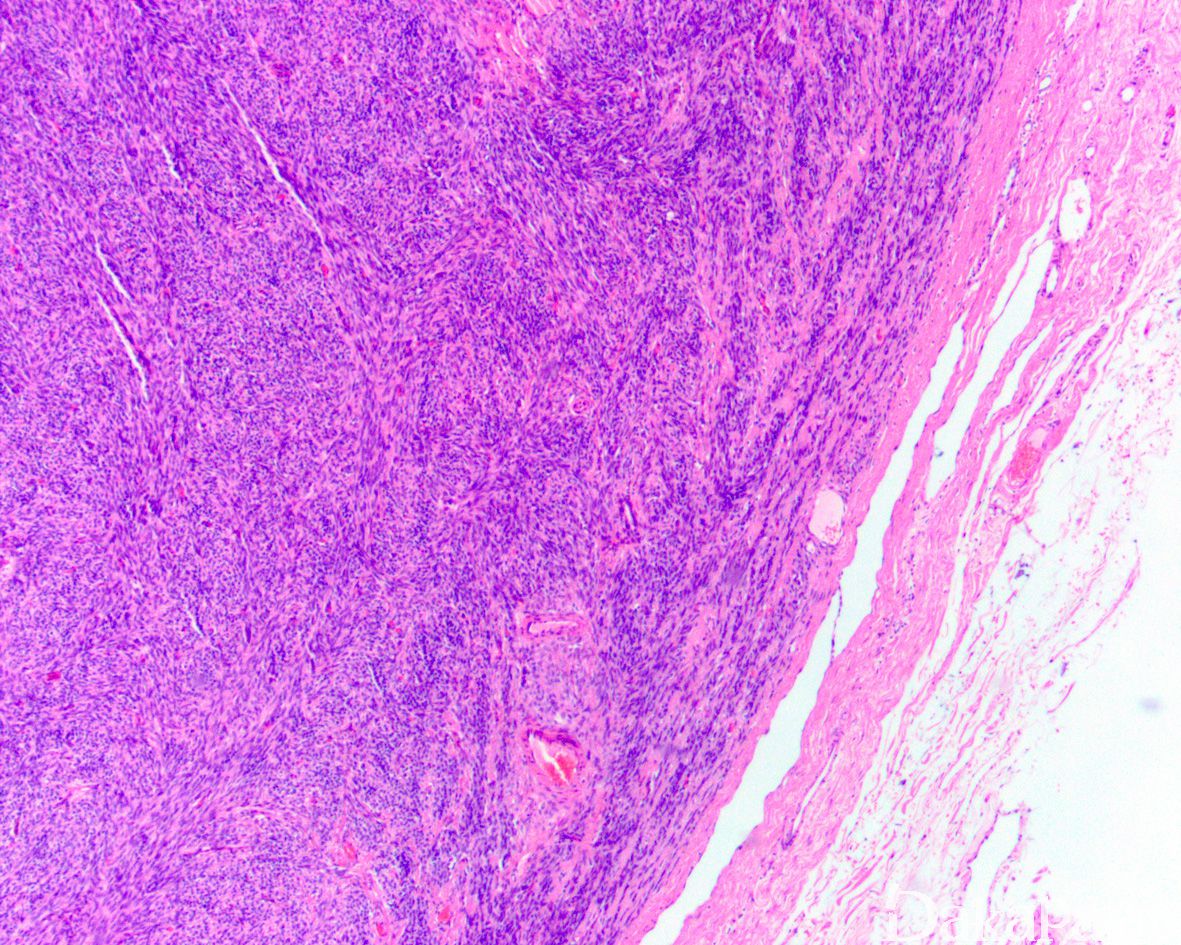

- 常发生于中老年患者,表现为睾丸肿胀;大体检查肿瘤为实性,切面黄-白色;

- 肿瘤具多少不等的性索和上皮细胞成分,其形态特征不符合支持细胞和粒层细胞肿瘤的诊断标准;

- 细胞异型轻重不一,核分裂像多少不等;

- 通常具明显的纤维性间质。